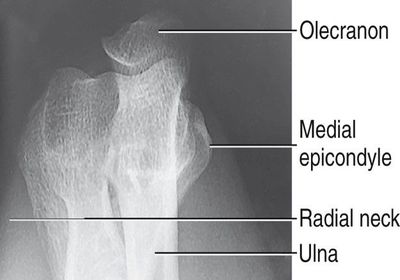

PROXIMAL ULNA A. olecranon process B. trochlear notch C. coronoid process D. radial notch (lateral)